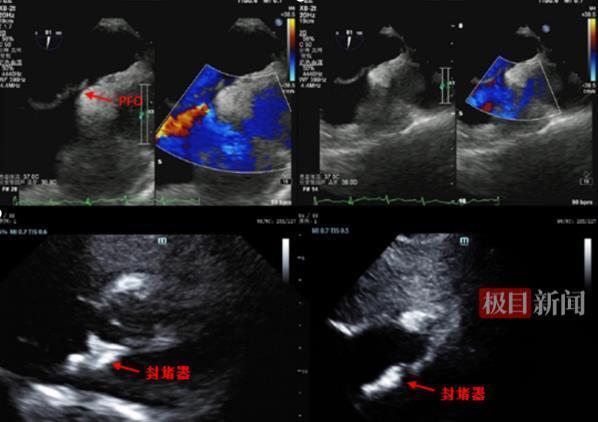

图片封堵器植入术

手术于10月30日进行。整个植入过程在超声引导下完成。术后检查显示,封堵器位置固定完美。患者术后恢复迅速,已于10月31日康复出院。